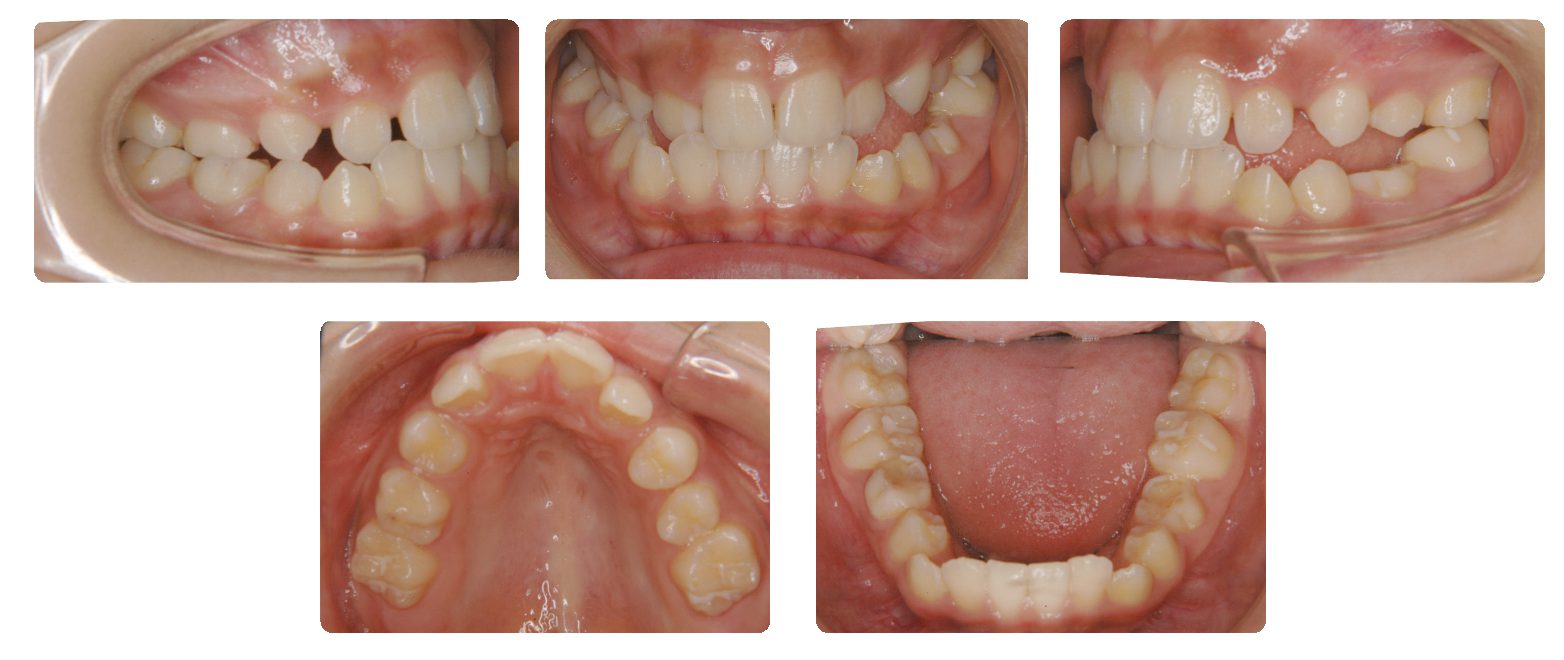

主訴:上あごの前歯が出ているが気になる 口を閉じにくい

初診時年齢:10歳

性別:女性

診断名:叢生

抜歯/非抜歯:非抜歯

装置名:可撤式拡大装置→マルチブラケット装置

上顎歯列の幅がかなり狭かったので側方への拡大を先行して拡大終了後に固定式装置により個々の歯を並べることにしました。

上あごの歯列幅を側方に拡大しながら左右犬歯の萠出スペースを少しずつ確保しました。永久歯がほぼ生え揃った時点で再診断を行い、非抜歯で治療を進めることになりました。